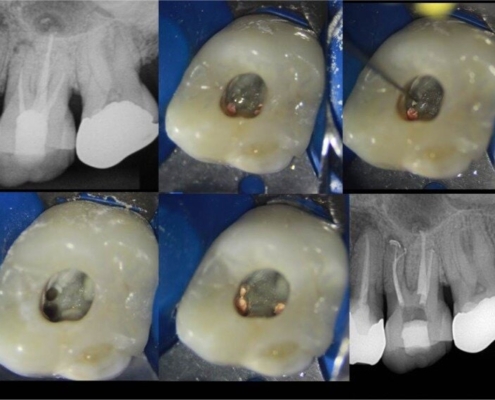

Tehnike pronalaska sekundarnog meziobukalnog kanala

Oblik obrisa pristupnog kaviteta prvog gornjeg kutnjaka trokutast je i smješten u mezijalnoj polovici zuba s osnovom prema bukalno i vrhom prema lingvalno (Slika 3.). Meziobukalni korijen vrlo je širok u bukolingvalnom smjeru, tako da je česta pojava manjeg sekundarnog meziobukalnog kanala. [8] Dno pulpne komore ima određena morfološka obilježja koja su od velike pomoći pri traženju kanala. Obično su na dnu vidljive linije koje vode prema ulazima u kanale i tvore zamišljenu „mapu“, odnosno rostrum canalis. [1] Primarni meziobukalni kanal smješten je blago distalno u odnosu na vrh meziobukalne kvržice, dok je manji sekundarni meziobukalni kanal smješten mezijalno od zamišljene linije koja povezuje primarni meziobukalni i palatinalni kanal, približno na udaljenosti 1 do 3 mm od primarnog. [4] Sam ulaz u sekundarni meziobukalni kanal teško je uočljiv kliničkom inspekcijom zbog dentinskog ramena koje ga pokriva i koje je potrebno ukloniti za lakši pristup kanalu. Osim dentinskog ramena, problem je i meziobukalni nagib ulaza te nagla zavijenost kanala u koronarnoj trećini prema mezijalno što ukazuje na najjednostavniji pristup iz distopalatinalnog kuta. [10] Upravo iz navedenih razloga, kako bi se poboljšala sama pristupačnost kanalu, potrebna je početna priprema i modifikacija pristupnog kaviteta u romboidni oblik uz oprez i minimalnu invazivnost. Istraživanjem je dokazano da je uklanjanje dentina s dna pulpne komore (tzv. troughing) do 2 mm od palatinalnog prema primarnom meziobukalnom kanalu korisna metoda te da su njezine prednosti nadmašile rizik od perforacije. [1] Potrebna je i dobra vizualizacija dna pulpne komore za što se koristi mikroskop, lupe ili barem intraoralno ogledalo s prednjom reflektirajućom površinom. Uz dobru pristupačnost i vizualizaciju lakše je istraživanje dna pulpne komore i traženje ulaza u kanal. Instrumenti poput DG16 Explorer (Slika 4.) ili tanki instrument poput D finder #10 (Slika 5.) od velikog su značaja za lociranje kanala. Iznimno su korisni i ultrazvučni instrumenti koji selektivno uklanjaju kalcifikacije u pulpi i čuvaju dentin od pretjerane štete te otkrivaju skriveni ulaz u kanal. Važno ih je pažljivo koristiti, laganim, kontroliranim pokretima kako bi se izbjeglo pretjerano uklanjanje dentina i iatrogena perforacija. Kod samog traženja kanala, irigacija može pomoći u njihovoj lokalizaciji. Natrijev hipoklorit ima antimikrobna svojstva, osigurava bolju vidljivost, smanjuje rizik od kontaminacije, omogućuje lakši pristup instrumentima te uklanja ostatke organskog materijala. Pulpni ostaci mogu reagirati s natrijevim hipokloritom pri čemu se stvaraju mjehurići, odnosno dolazi do stvaranja kisika, što je pokazatelj položaja ulaza u kanal te potencijalnog postojanja novih, neotkrivenih kanala. Uz natrijev hipoklorit, kao dijagnostičko sredstvo za lociranje kanala upotrebljava se i kemijski spoj 1% natrijev fluorescein. To je oftalmološka otopina koja ima svojstvo vezanja za vezivno tkivo i svijetli kada se izloži plavom svjetlu. Nalapatti i Glassmann predložili su njegovu upotrebu, na način da se otopina aplicira u pulpnu komoru i ostavi da djeluje i reagira 2 minute. [1] Aplikaciju je potrebno obaviti oprezno i paziti na određeni vremenski interval djelovanja, budući da postoji rizik od obojenja zuba. Nakon toga potrebno ju je izložiti plavom polimerizacijskom svjetlu, a kanale promatrati mikroskopom. Važno je obilno isprati pulpnu komoru natrijevim hipokloritom nakon završenog postupka. Na temelju te tehnike, napravljen je i veliki pomak u razvitku mikroskopa, odnosno kobaltno-plavog filtra koji omogućuje još precizniju i jednostavniju primjenu natrijevog fluoresceina. [1] Još jedan vrijedan dijagnostički alat, koji nam omogućuje trodimenzionalan prikaz anatomije jest CBCT (konusna kompjutorizirana tomografija). Ova tehnologija omogućuje bolju vizualizaciju, prepoznavanje varijacija, planiranje samog pristupa, minimalno invazivnu preparaciju te veću predvidivost terapije (Slika 6.). Kliničkom studijom dokazano je da je učinkovitost korištenja CBCT-a u pronalaženju dodatnih sekundarnih meziobukalnih kanala u maksilarnim kutnjacima ograničena te je sam kanal bio prikazan u 33 % slučajeva. [11]

Instrumentacija kanala

Budući da meziobukalni primarni i sekundarni kanal često pripadaju tipu II konfiguracije prema Vertucciju te da postoji varijabilnost položaja kanala, nameću se specifični zahtjevi njihove obrade. Upravo zato se klinički smatra racionalnim i tehnički opravdanim u potpunosti instrumentirati i oblikovati MB1 kanal prije početka instrumentacije MB2. Obrada kanala često predstavlja izazov zbog izrazite mezijalne zakrivljenosti u koronarnom dijelu kanala. Nakon lokalizacije ulaza prvi korak je sondiranje kanala malim ručnim instrumentima veličine ISO #08–#10. U ovom koraku nije nužno dosegnuti vanjski otvor kanala. Za širenje ulaza u korijenske kanale korisni su nikal titanski rotacijski instrumenti za proširenje ulaza u kanal (eng. orifice opener) koji se primjenjuju u blagim kretnjama iščetkavanja, usmjerenim od furkacije (Slika 7.). Takav pristup stavlja naglasak na očuvanje strukturnog integriteta korijena, jer omogućuje selektivno uklanjanje dentina bez nepotrebnog slabljenja stijenki kanala u „opasnoj zoni ”. Opasne zone su zabilježena područja korijenskih stijenki gdje je dentin, u prosjeku, značajno tanji, što povećava predispoziciju za nastanak mehaničkih uzdužnih perforacija (eng. strip perforation) tijekom agresivne obrade. Korisno je znati da je debljina dentina mezijalnog korijena u području prema furkaciji, tj. na distalnoj stijenci MB2 kanala, u približno 77 % slučajeva manja je od 1 mm. [12] Nakon toga se radi predinstrumentacija ručnim instrumentima veličine ISO #15–#20 ili strojnim instrumentima kako bi se uspostavila sigurna radna putanja (eng. glide path). U starijih pacijenata ili kod zuba s opsežnim restauracijama, MB2 kanal često bude kalcificiran, što značajno otežava instrumentaciju. U takvim slučajevima preporučuje se kombinacija rigidnijeg ručnog instrumenta sa 17 % EDTA otopinom. [13] Balanced force tehnika instrumentacije prikladna je za zakrivljene i uske kanale jer omogućuje očuvanje originalne putanje, smanjenje torzijskog stresa instrumenta i očuvanje strukturalnog integriteta korijena. Ona predstavlja sustavan pristup ručnoj instrumentaciji zakrivljenih kanala, temeljen na izmjeničnim rotacijama instrumenta i preciznom pritisku operatora. Ručni se instrument inicijalno uvodi u kanal i okreće u smjeru kazaljke na satu, čime se njegove režuće površine utiskuju u dentin. U ovoj fazi koriste se K-fleksibilni (K-Flex) instrumenti koji su zbog svoje elastičnosti i specifičnog dizajna pogodni za ovu tehniku. Ovaj početni korak omogućuje kontrolirano pomicanje instrumenta prema apikalno pri čemu spiralni raspored žljebova i progresivni konus potiskuju režuće bridove dublje u stijenke kanala, stvarajući stabilnu radnu putanju. Operator osjeća silu potrebnu za zahvaćanje dentina, što pruža taktilnu povratnu informaciju o napredovanju instrumenta. Nakon toga, instrument se rotira suprotno od kazaljke na satu, dok operator primjenjuje lagani pritisak prema apikalno. Kada tlak premaši sile smicanja dentina, dolazi do kontroliranog rezanja, što omogućuje preciznu kontrolu svakog reznog koraka. Od drugih, često korištenih tehnika ručne instrumentacije, valja spomenuti i crown-down tehniku koja se, po mnogo čemu, pokazala superiornijom od klasične step-back tehnike kada su u pitanju uski korijenski kanali s kutom zakrivljenosti od 10 do 35 stupnjeva. Shodno tomu, izvrsne rezultate pokazuje hibridna tehnika, koja objedinjuje prednosti obje metode. Klinički protokol započinje instrumentacijom koronarne trećine crown-down tehnikom čime otvaramo liniju pristupa za dublje dijelove. Potom slijedi instrumentacija apikalne trećine, te se konačno uniformno proširenje kanala postiže step-back tehnikom u srednjoj trećini. Kod odabira strojnih instrumenata treba imati na umu termičke fazne transformacije NiTi legura te odabrati sustav koji omogućuje iznimnu fleksibilnost i precizno praćenje prirodnih zakrivljenosti kanala, što je karakteristika sustava s dominantno martenzitnom fazom. Primjerice, Protaper Next pokazuje visoku otpornost na ciklički zamor u zakrivljenim kanalima zahvaljujući kombinaciji M-Wire legure i varijabilnog konusa instrumenta (Slika 8.). [14] Takva svojstva omogućuju sigurno vođenje instrumenta kao i očuvanje originalnog oblika kanala i integriteta stijenki. Preporuka je da se širenje kanala ograniči na instrument #25, jer istraživanja pokazuju da instrumenti #30 ili veći značajno smanjuju debljinu preostale distalne stijenke MB2 kanala na manje od 0,3 mm. [12] Takva debljina smatra se kritičnom za podnošenje sila koje nastaju tijekom lateralne kondenzacije gutaperke, a istovremeno povećava rizik od vertikalne frakture korijena. Vrlo uspješne kliničke rezultate pokazuje TruNatomy od Maillefera koji je specifično kreiran kako bi se optimizirala instrumentacija uskih i zavijenih kanala. Ekscentrični dizajn smanjuje lokalno naprezanje instrumenta te reducira torzijski stres, a gracilniji, “slim” dizajn i regresivni konus omogućuju očuvanje tvrdog zubnog tkiva u cervikalnom dijelu (Slika 9.). [15] S druge strane, nakon pažljive ručne instrumentacije i formiranja sigurne radne putanje, moguće je koristiti Reciproc sustav, načinjen od M-Wire legure, a koji omogućuje obradu kanala sa samo jednim instrumentom, tzv. “single file” koncept. Ovaj sustav primjenjuje reciprocirajuću kinematiku s rotacijom od 150 stupnjeva u smjeru suprotnom od kazaljke na satu i 30 stupnjeva u smjeru kazaljke na satu. Međutim, zbog velike koničnosti standardnih Reciproc instrumenata, danas je na tržištu dostupna novija varijanta, sustav Reciproc Minima, koji je zahvaljujući gracilnijem dizajnu i naprednijoj leguri prikladniji za obradu MB2, osobito u kombinaciji s prethodnim ručnim širenjem kanala. [14]